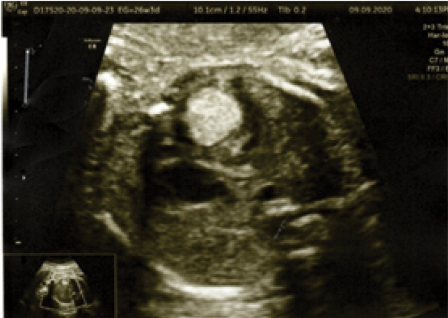

Rhabdomyomas are rare fetal cardiac tumours that may be present in up to 86 % of newborns. They are mostly found in the interventricular septum, atrial or ventricular free wall and infrequently in the atrioventricular valves. It depends on the size of the tumour to have fetal haemodynamic repercussions.

Ultrasound examination shows a hyperechogenic lesion in the interventricular septum with protrusion into the right ventricular cavity, accompanied by mild deviation of the interventricular septum and associated at the time of examination with ventricular arrhythmia.